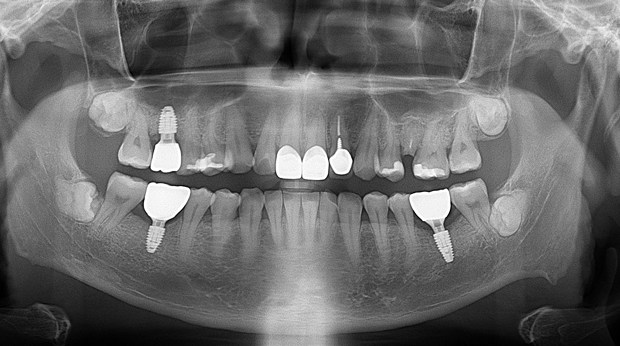

의식하진정법(수면마취)/임플란트

임플란트와 사랑니 발치는 외과적 시술로 잇몸을 절개하는 외과적 시술은

짧으면 짧을 수록 시술 후 붓기와 통증이 최소화됩니다.

치과의사 경력 14년차 구강외과 전문의가 빠르고 안전하게, 아프지 않게 수술해 드립니다.